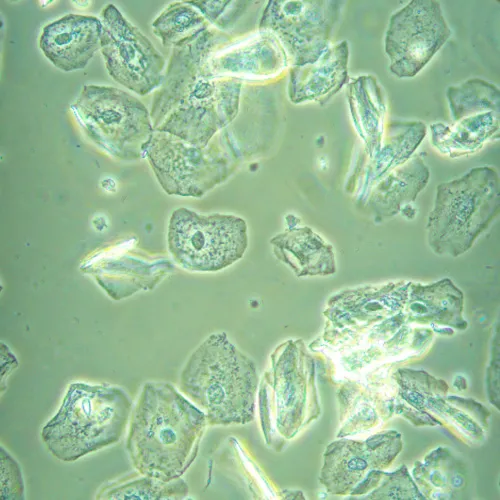

Kutatási célú mikroszkóp. A mikroszkópot kicsapódott folyadékok, sejtkolóniák, élő sejtek, szövetkultúrák, valamint egyéb festett és nem festett minták laboratóriumi üvegárukban történő tanulmányozására terveztük. A mikroszkópot a fordított kialakításának köszönhetően Petri-csészékkel, soküreges lemezekkel, fiolákkal, hengeres palackokkal és 1,2 mm fenékvastagságú, legfeljebb 75 mm- lombikokkal is lehet használni. A mikroszkóp speciális objektíveket használ az ilyen üvegedényekkel való munkához. A kondenzor eltávolításával megfigyelhetők a sejttenyészetek Petri-csészékben vagy legfeljebb 187 mm magas hengeres lombikokban. A megfigyelések áteső fényben, világoslátóterű, fáziskontraszt és dombor-kontraszt technikák alkalmazásával lehetségesek. Opcionális komponensek lehetővé teszik a Hoffman modulációs kontraszt technikák alkalmazását is. A mikroszkóp 5 MP felbontású, USB 3.0 interfésszel rendelkező kamerával rendelkezik. A kamera számítógéphez csatlakozik, és a képet annak képernyőjén jeleníti meg. A szoftver elemzési és dokumentációs funkciókkal egészíti ki a rendszert. A kamera a mikroszkóphoz a mellékelt 0,5x vagy 1x adapter segítségével csatlakoztatható. Az adapter kiválasztása a megoldandó feladatoktól függ. A 0,5x adapter növeli a látómezőt, míg az 1x adapter a képet "változatlanul" továbbítja, az élek levágásával, ugyanakkor minden részlet nagyobbnak látszik az érzékelőn. A mikroszkóp az orvostudomány, a farmakológia, a biológia és a virológia területén zajló kutatásokra szolgál.

- Tudományos kamera 20x, 40x, 60x és 100x objektívekkel történő világos látóterű megfigyelésekhez

- 5 MP-es felbontás: közepes nagyítású objektívekkel történő megfigyelés esetén a kamera a finom részleteket is képes megjeleníteni